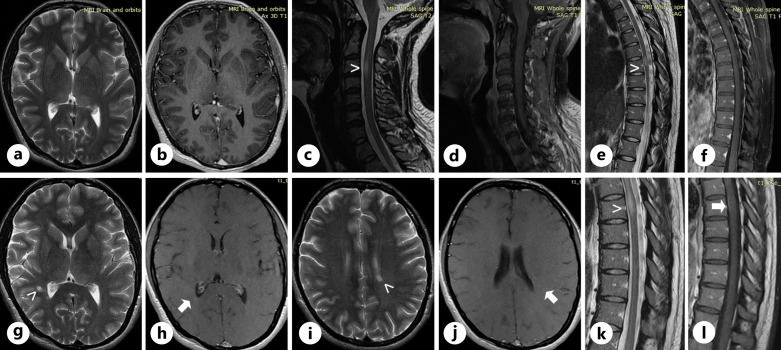

Case presentation: In this study, we describe the case of a 27-year-old woman who presented with signs and symptoms of optic neuritis and was then diagnosed with both MS and NF1. As the patient continued to experience MS relapses despite initial interferon-beta treatment, she was subsequently switched to natalizumab and responded well.

Conclusion: This case illustrates how MRI lesion differentiation with the co-existence of MS and NF1 can be difficult due to overlaps in lesion characteristics, while treatment decisions can be challenging mainly due to scarce data on the oncogenic risk of MS immunomodulary therapies. Therefore, clinicians need to balance out the risk of malignancy development with the risk of progressive neurological disability when treating such patients.